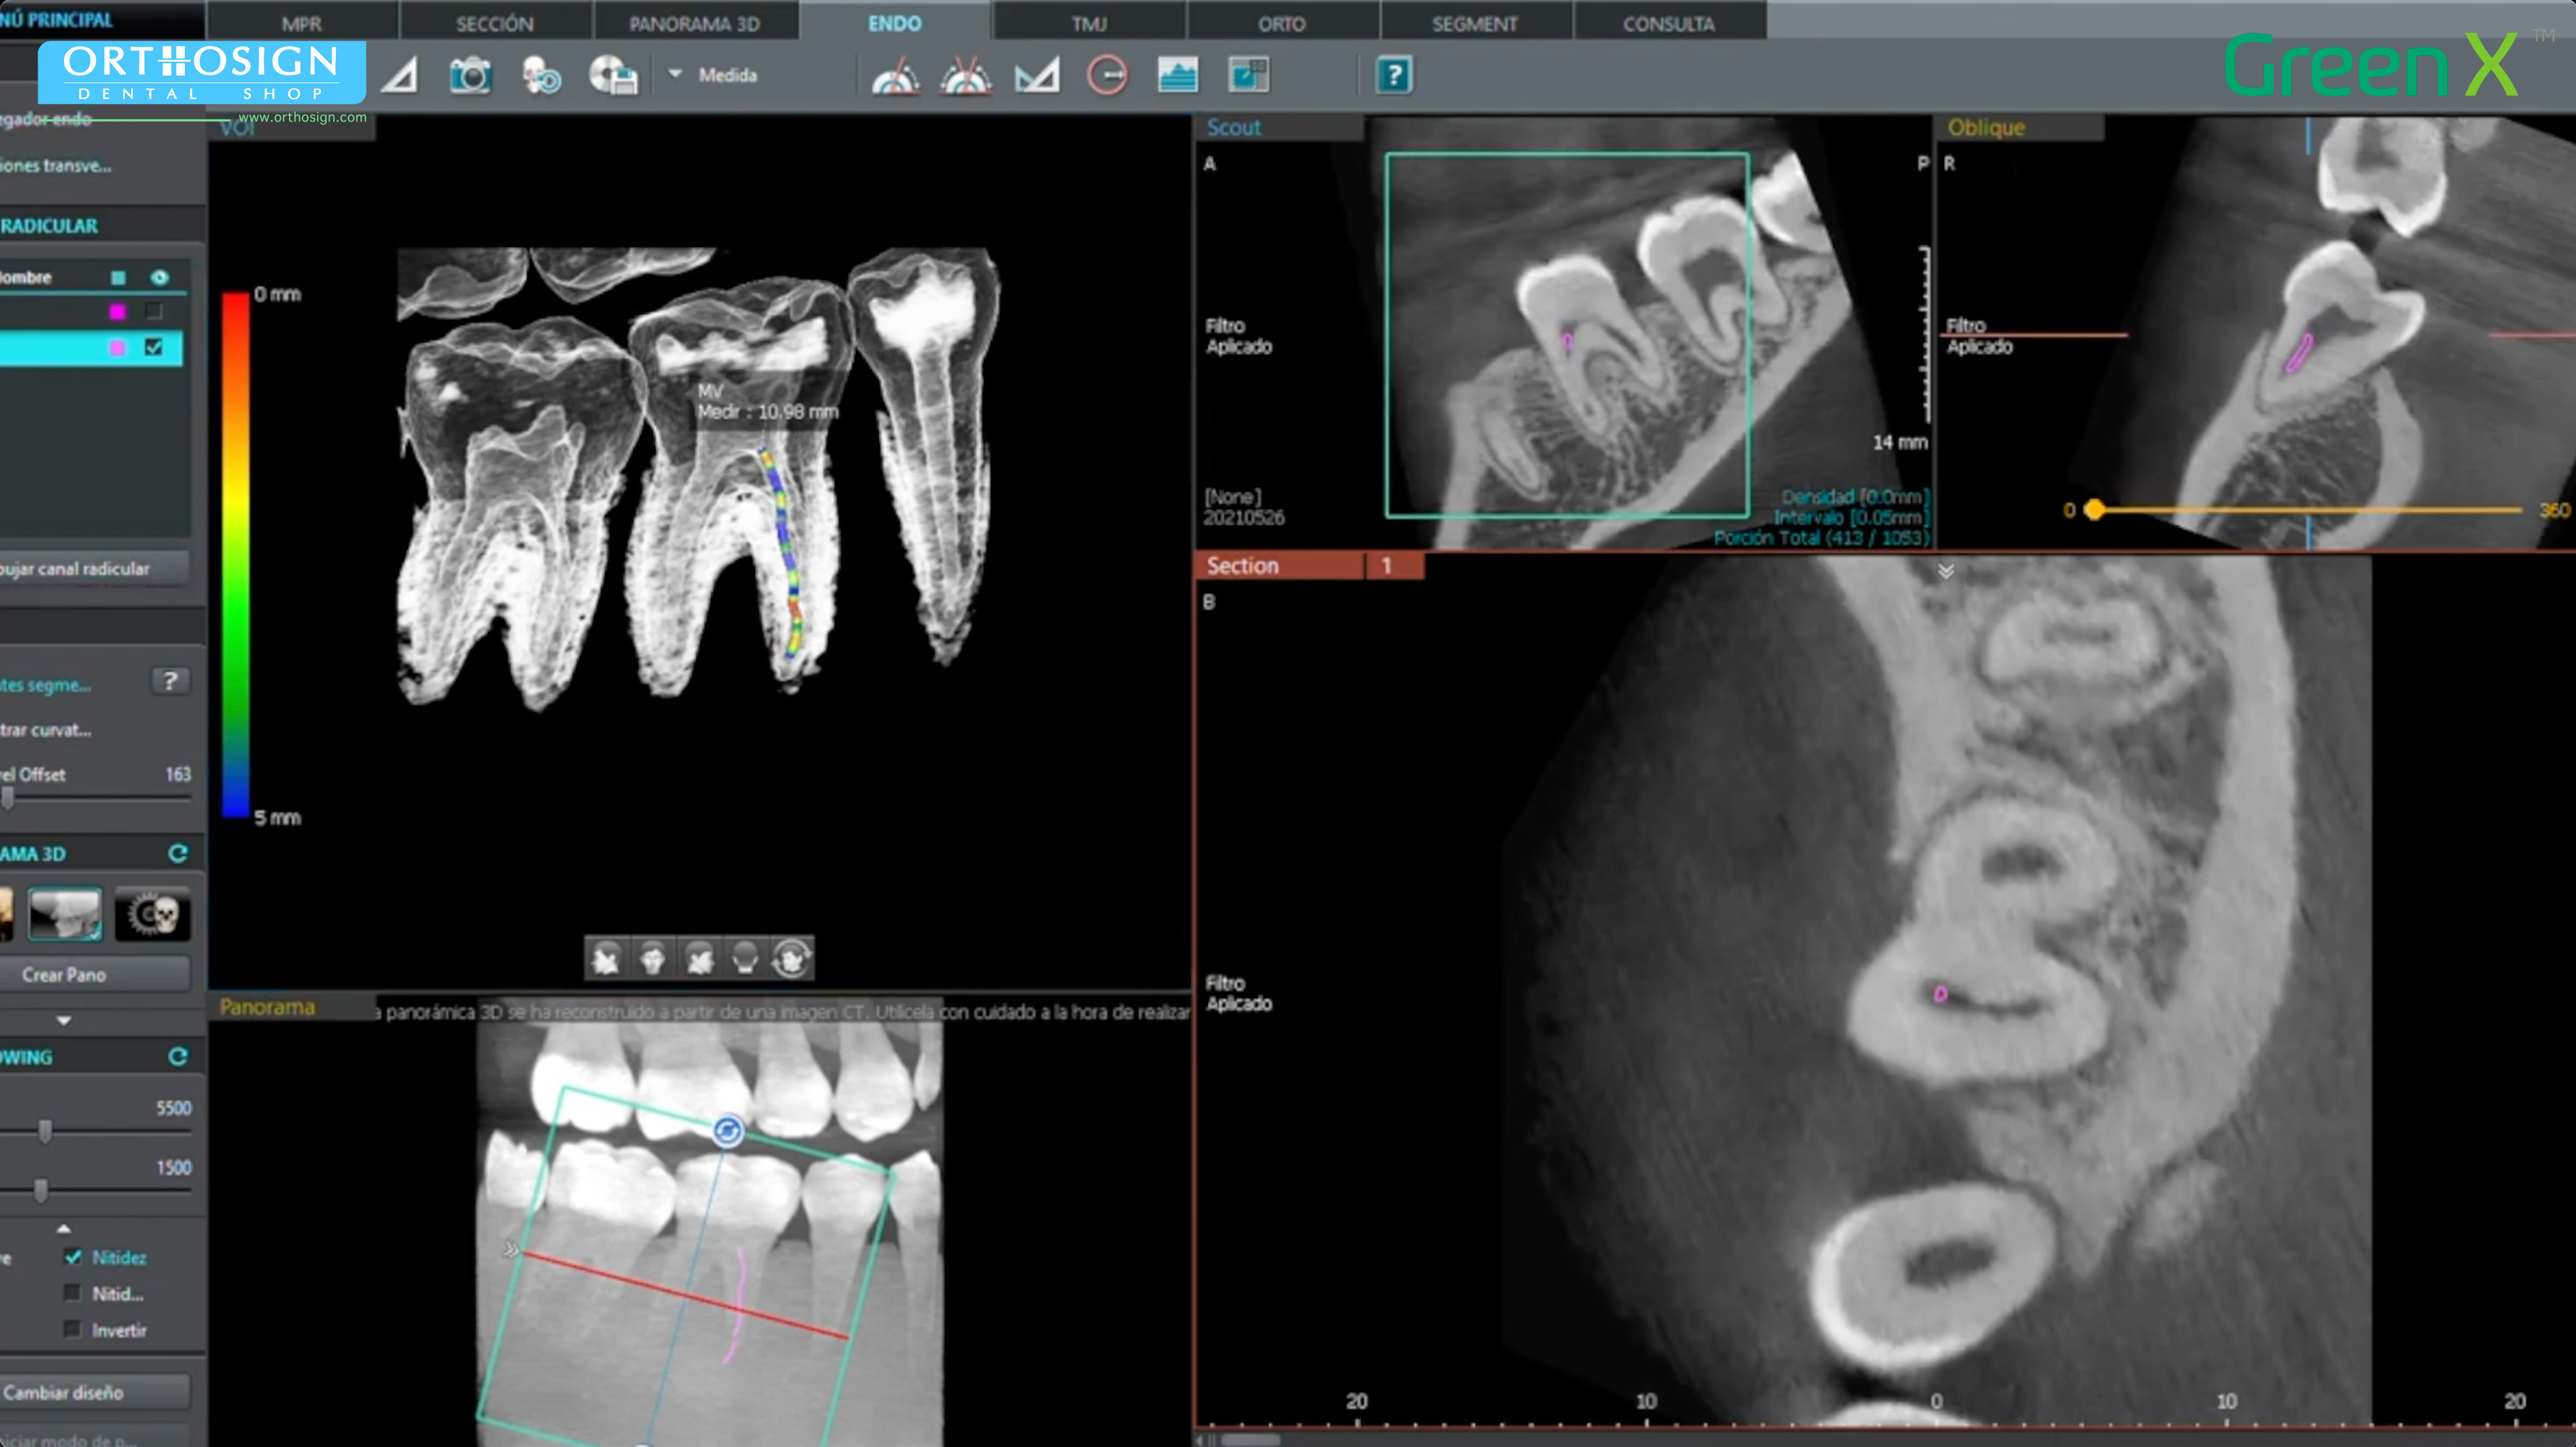

- Modo ENDO con alta resolución 4 x 4 cm (Voxel de 0.05 mm.).

- Radiografía Panorámica (ortopantomografía).